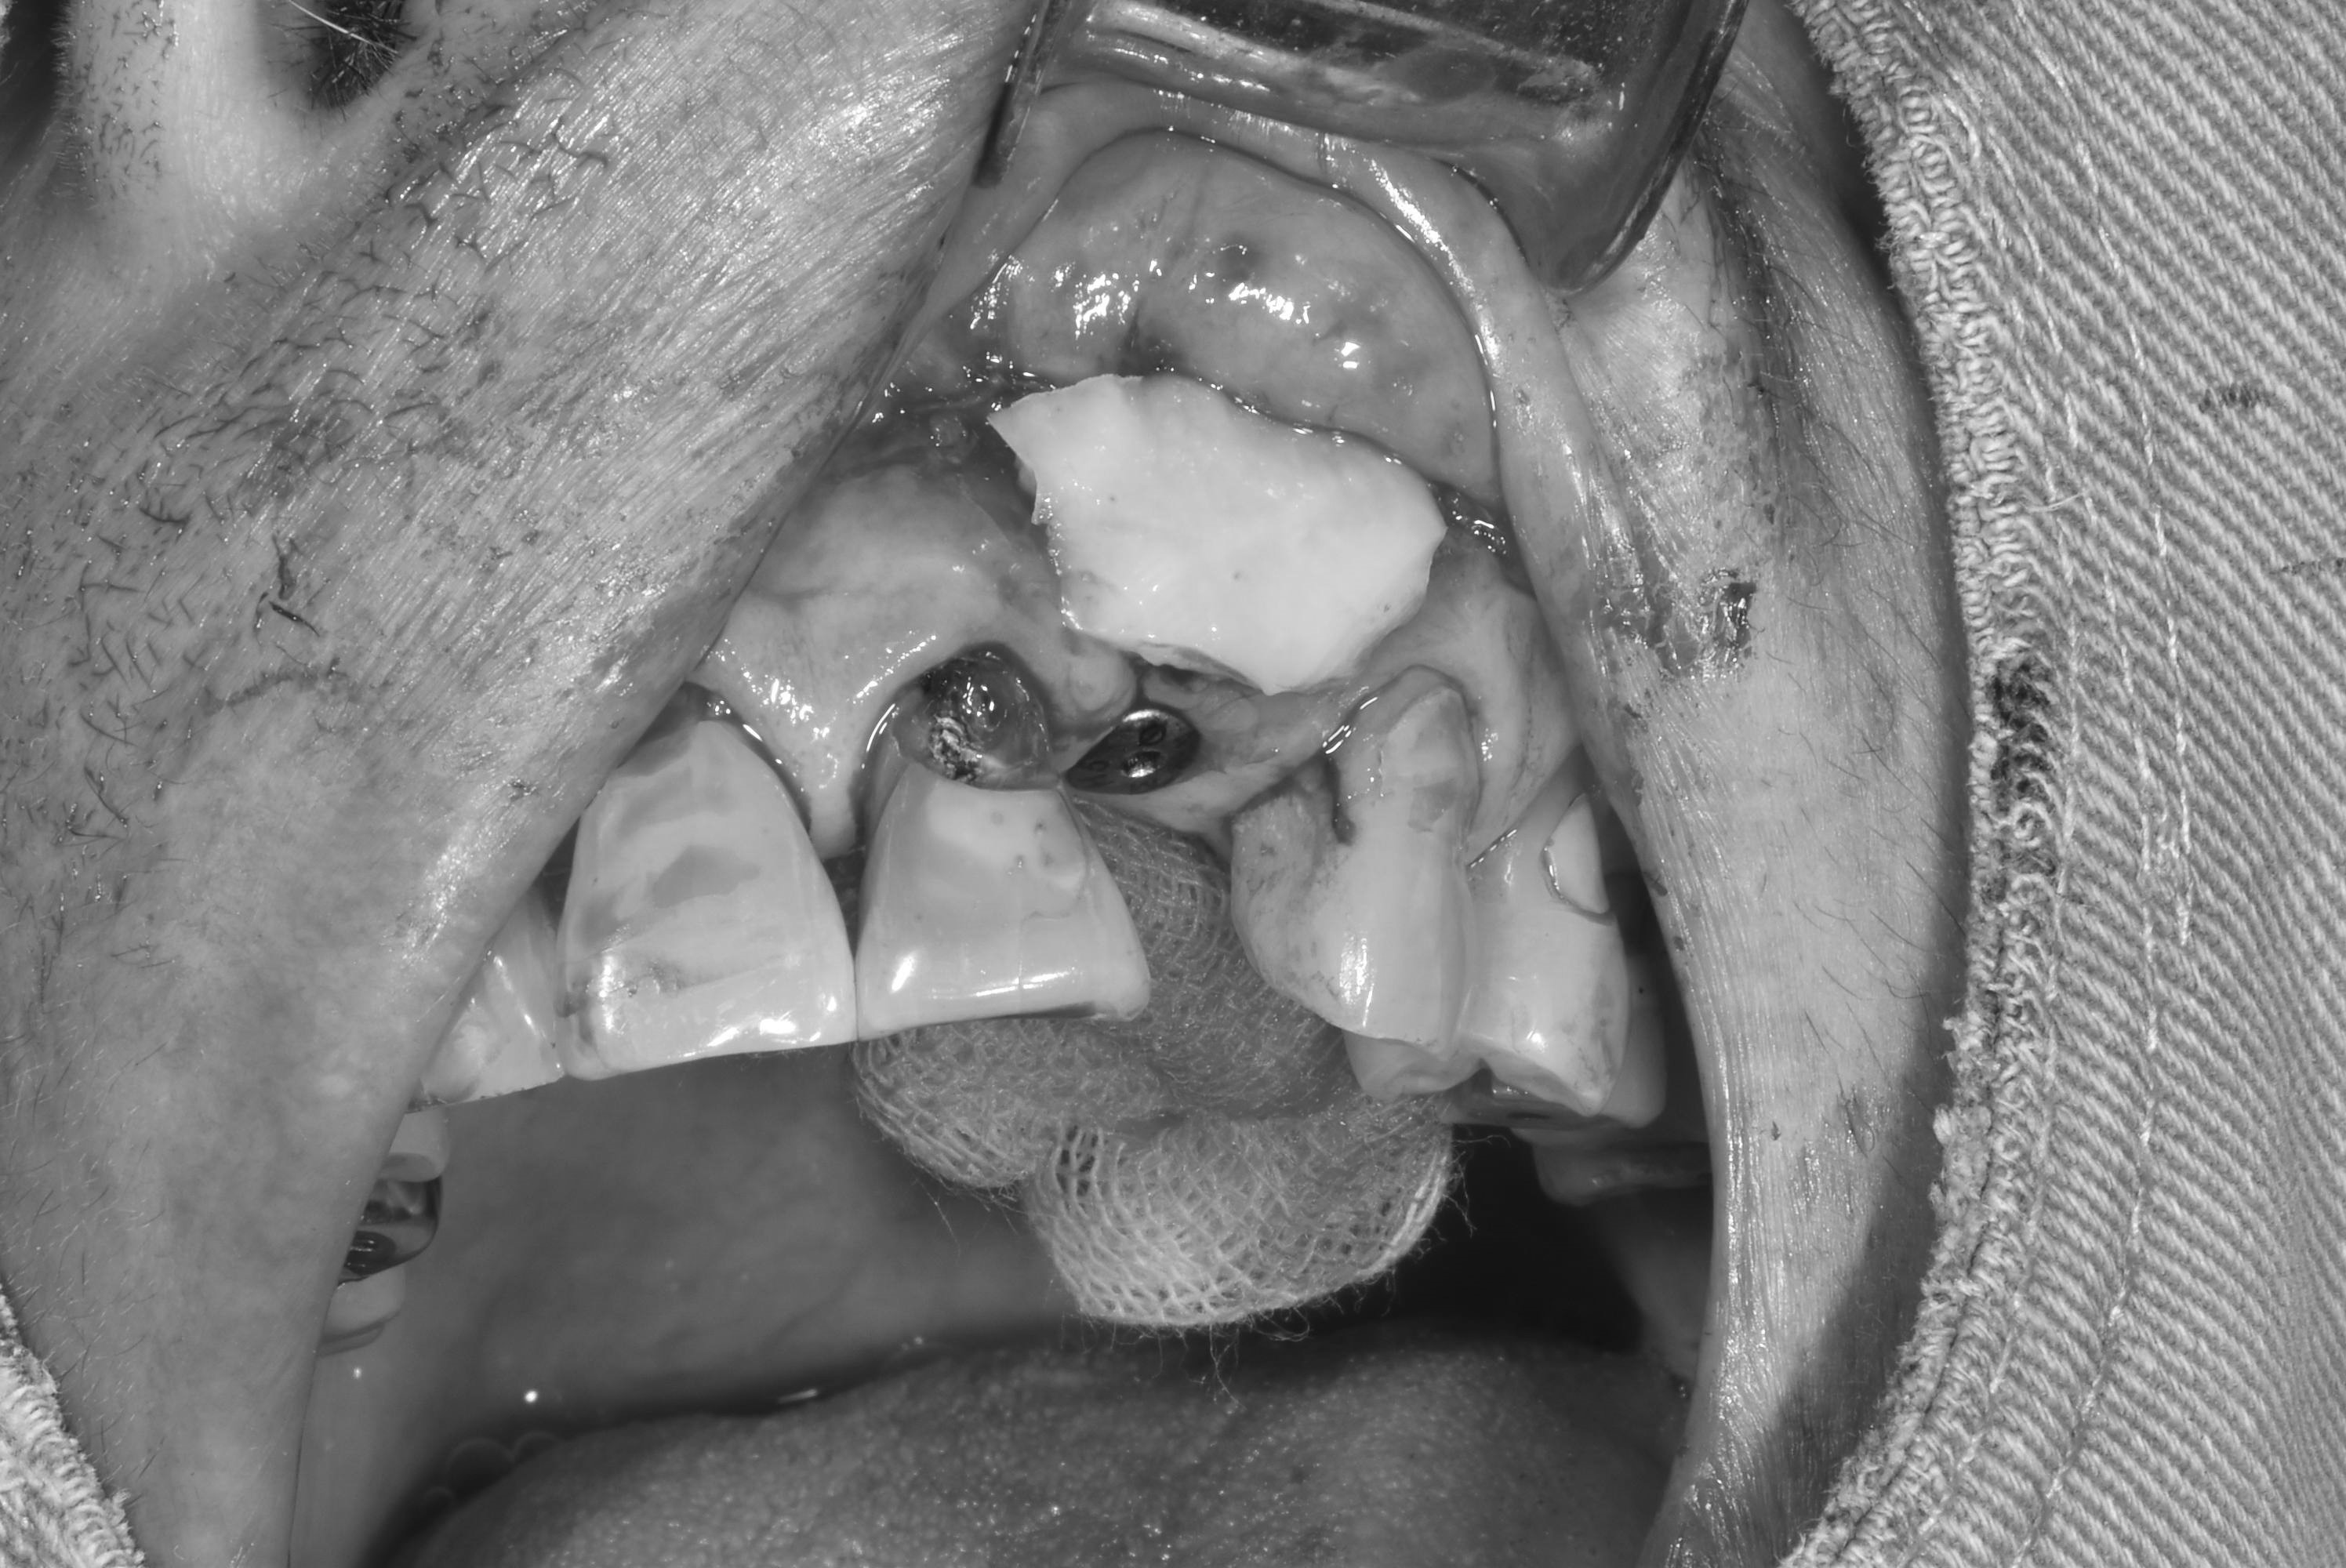

牙齦移植術(補肉)

手術案例

術前加術後案例

案例三